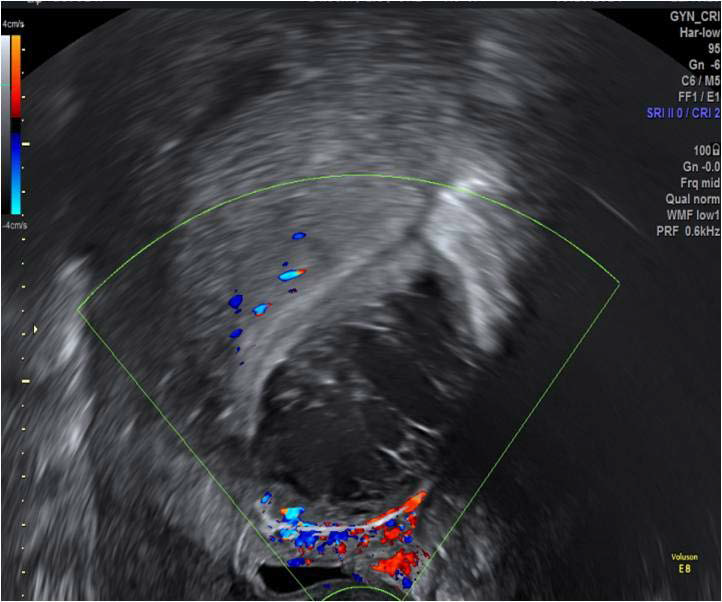

Figure 12: Colour Doppler shows a non-vascular mixed echogenicity haematomaoriginating from the anterior uterine wall, posterior to the urinary bladder (sagittal plane on transvaginal scan).

figure 12